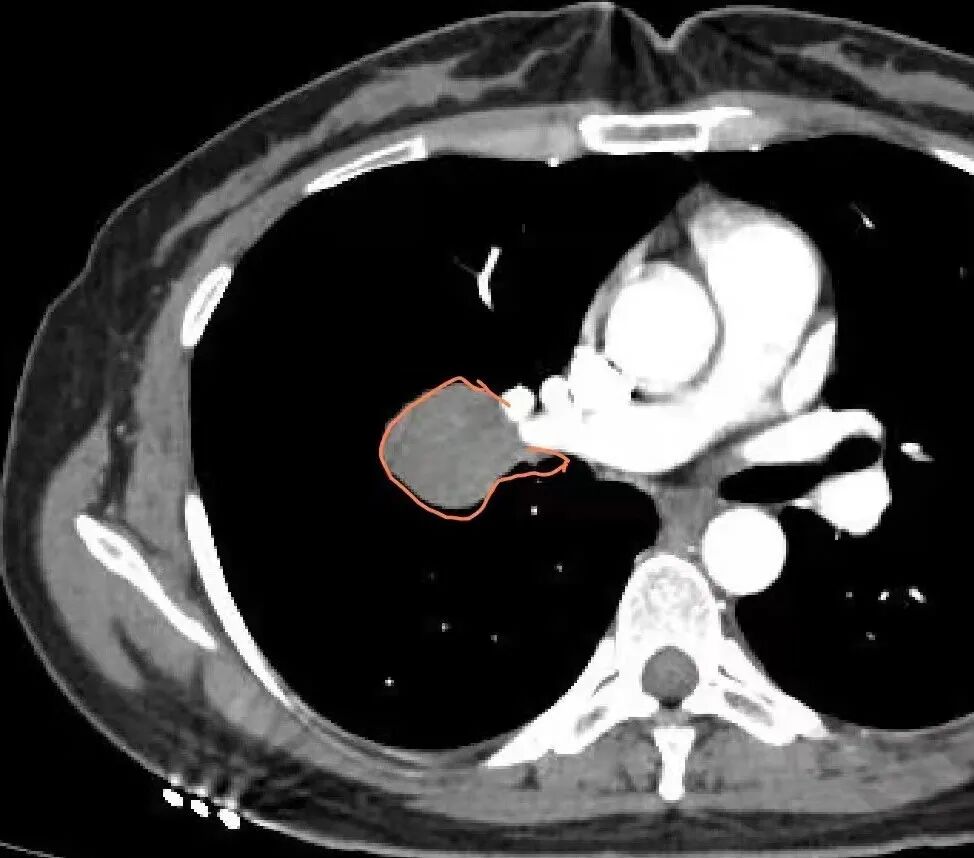

3.病灶密度均匀,未见液化坏死、钙化及脂肪低密度。轻度强化,可见纤细血管影蜿蜒穿行。右肺动脉推移变形,未见侵入或充盈缺损。

3)硬化性肺细胞瘤(PSP)可以血管贴边,常常强化比较显著。

4)发生于肺表面(近脏层胸膜或叶间裂),强化不显著,可见穿行血管,与本例的符合程度是最高的。